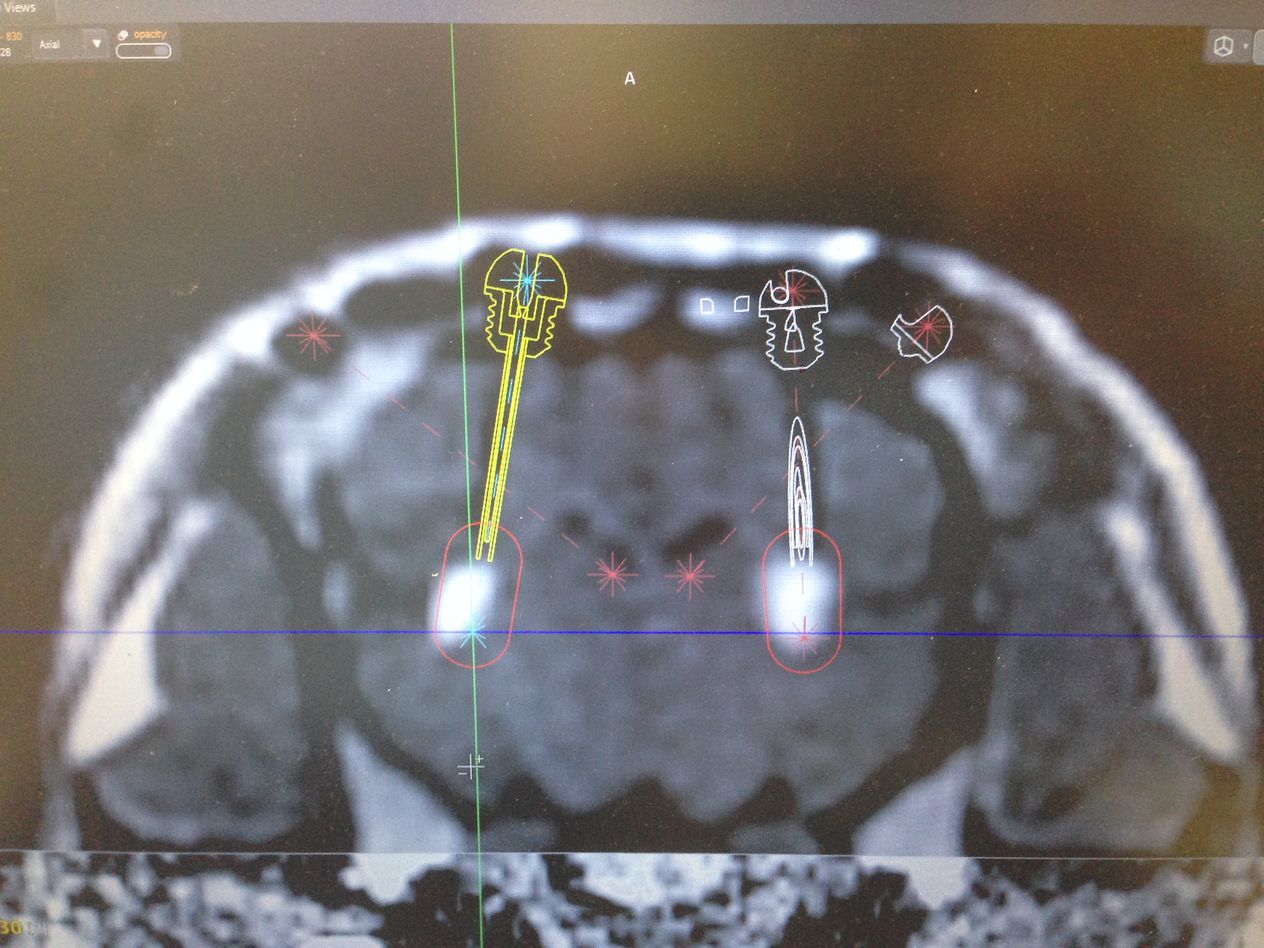

Přistoupili jsme k druhé studii, kdy už byl do viru vložen léčebný přípravek s miRNA (micro RNA), později pojmenovaný jako přípravek AMT130, a sledovali jeho účinnost. Na základě pozitivních výsledků, tedy výrazného snížení lidského huntingtinu jsme v roce 2017 spustili sérii testů na dvaceti prasatech, kdy jsme látku aplikovali do mozku kontrolovaně pomocí magnetické rezonance. Za pomoci stereotaktického nástavce a skenu z magnetické rezonance jsme navrhli koordináty, které pak použili neurochirurgové z Nemocnice na Homolce Roman Liščák a Dušan Urgošík pro navrtání malé dírky do mozku a umístění katetrů, kterými se látka pomalu do mozku aplikovala.